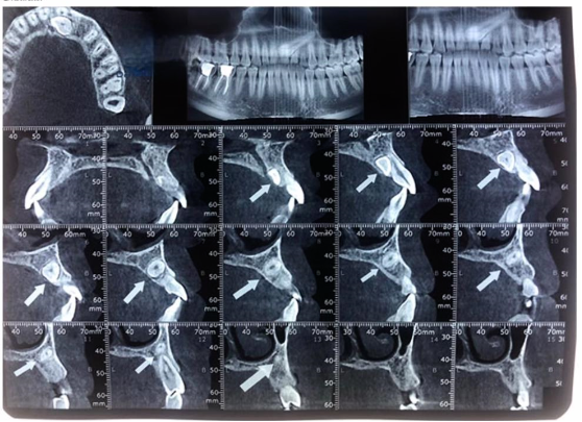

برای تشخیص نهفتگی دندان متخصص شما را به انجام عکسبرداری و رادیوگرافی ارجاع می دهد. یک رادیوگرافی OPG حتما مورد نیاز است. در بعضی موارد برای تشخیص دقیق محل دندان نیاز به رادیوگرافی تکمیلی از جمله رادیوگرافی اکلوزال, لترال سفالومتری و یا CBCT می باشد.

نمونهی CBCT مربوط به نهفتگی